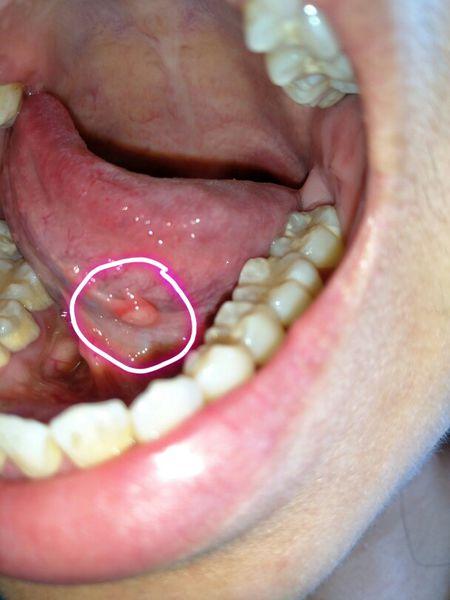

请问一下我这个是不是舌下腺囊肿?

舌下腺囊肿

舌下腺囊肿图片 早期

舌下腺肿大

舌下腺囊肿能自愈吗

舌下腺发炎的图片

口腔舌下腺小疙瘩图片

舌下腺发炎症状图片

舌下阜长疙瘩图片